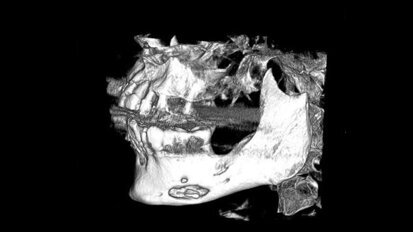

Minimalnie inwazyjne rozwiązania implantoprotetyczne w zaniku poziomym kości szczęki i żuchwy

Autorzy przedstawiają przypadki pacjentów z bardzo zaawansowanym poziomym zanikiem kości szczęki i żuchwy. Na podstawie szczegółowej ...